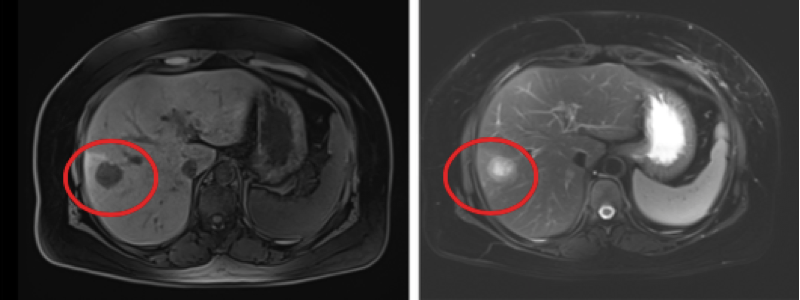

【经典病例】慢性活动性EBV感染致肝损害

281x200 - 37KB - PNG